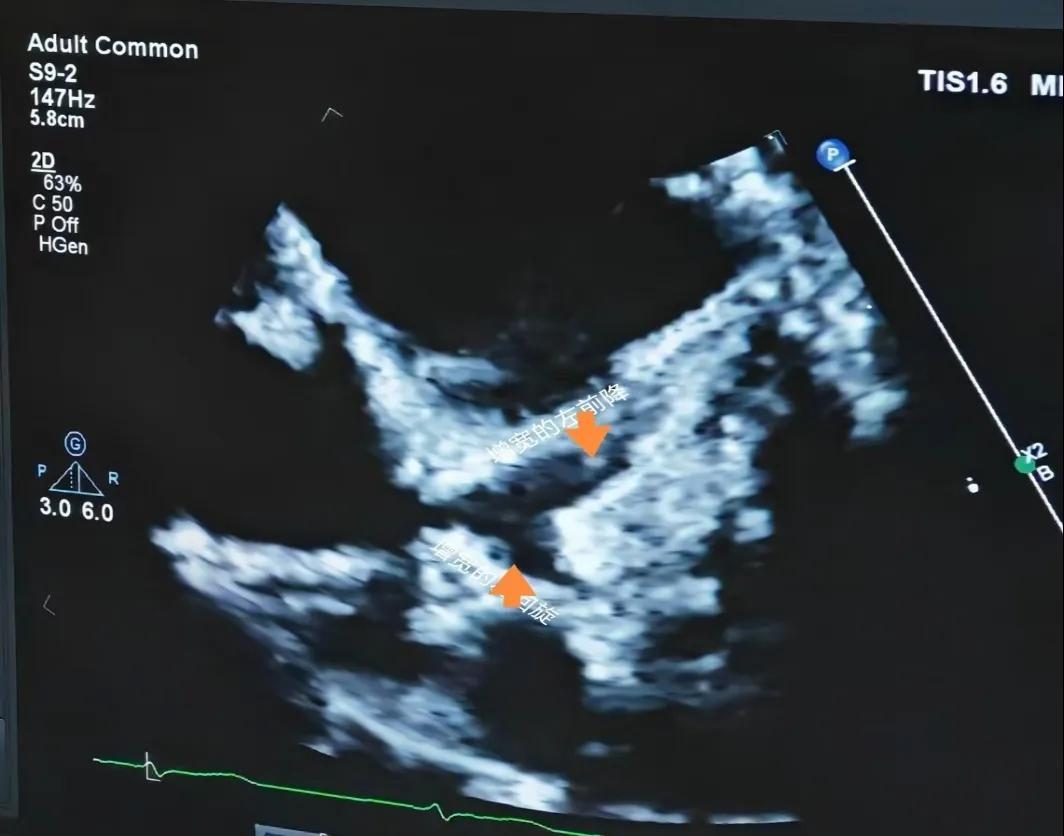

(川崎病患兒:增寬的左前降支和左回旋支)

(川崎病患兒:左冠狀動(dòng)脈瘤)